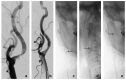

Background/Objectives: This study aimed to evaluate the incidence, risk factors, clinical implications, and rescue maneuvers of technical complications related to embolic protection devices (EPDs) during carotid artery stenting (CAS). Materials and Methods: We retrospectively reviewed all patients who had undergone CAS with EPDs between April 2018 and March 2024. The incidence and types of technical complication associated with EPDs were assessed. Clinical, angiographical, and procedural factors were analyzed to identify risk factors for the occurrence of EPD-related adverse events. Various rescue techniques for managing adverse events were investigated based on the procedure record. Results: Of the 158 enrolled patients, the rate of EPD-related technical complications was 23.4% (n = 37). Among them, complicated filter retrieval was the most common adverse event (n = 23, 14.6%). Older age, a higher degree of residual stenosis, and the type of the EPD were significant risk factors for complicated filter retrieval (p < 0.05). Although distal thrombus migration requiring thrombectomy was more frequent in patients with complicated filter removal (2.2% vs. 13.0%, p = 0.041), there was no significant increase in postprocedural thromboembolic and hemorrhagic complications. When complicated filter retrieval occurred, careful to-and-fro movement of the patients' neck, such as rotation, or asking them to swallow was tried first in all 23 patients. When these attempts failed, manipulation of a curved-tip guiding catheter, the balloon bridge technique, and alternative use of a 5 Fr angiocatheter as a retrieval sheath were sequentially tried, and all filters were successfully retrieved. Conclusions: Complicated filter retrieval was the most common technical complication during CAS. Various rescue techniques for successful filter removal were effective for ensuring safety of CAS.